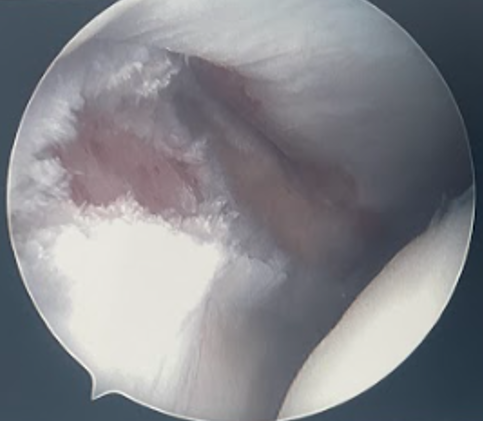

- talar dome and tibial plafond for chondral lesions

Talar dome